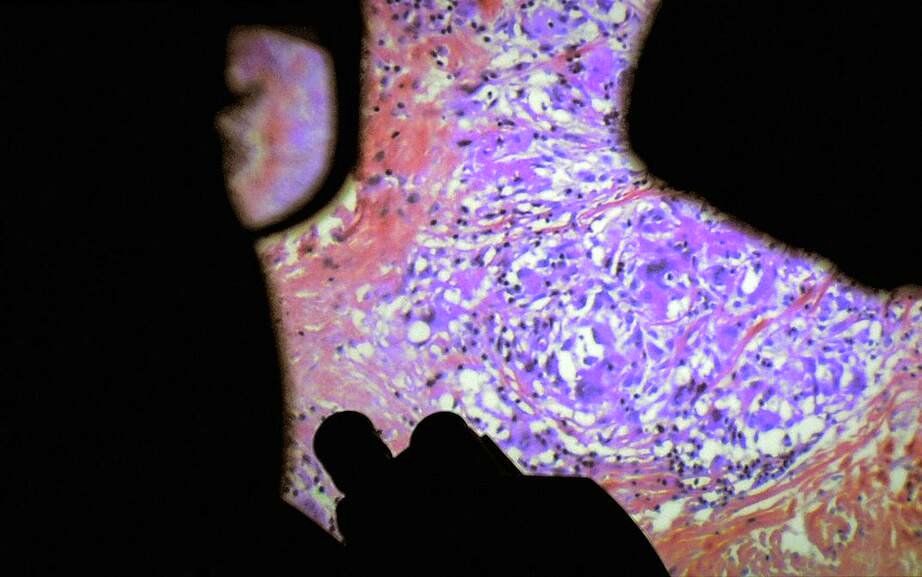

Five centuries ago, anatomist André Vésale opened up the human body to science for the first time in history. Today, De Humani Corporis Fabrica opens the human body to the cinema. It reveals that human flesh is an extraordinary landscape that exists only through the gaze and attention of others. As places of care, suffering and hope, hospitals are laboratories that connect every body in the world.